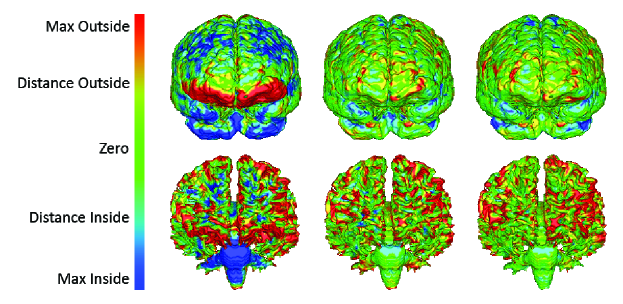

A primal-dual based optimization framework has been recently proposed in [127, 128] for the problem of deformable registration/fusion, which forms one of the most central and challenging tasks in medical image analysis. This problem consists of recovering a nonlinear dense deformation field that aligns two signals that have in general an unknown relationship both in the spatial and intensity domain. In this framework, towards dimensionality reduction on the variables, the dense registration field is first expressed using a set of control points (registration grid) and an interpolation strategy. Then, the registration cost is expressed using a discrete sum over image costs projected on the control points, and a smoothness term that penalizes local deviations on the deformation field according to a neighborhood system on the grid. One advantage of the resulting optimization framework is that it is able to encode even very complex similarity measures (such as normalized mutual information and Kullback-Leibler divergence) and therefore can be used even when seeking transformations between different modalities (inter-deformable registration). Furthermore, it admits a broad range of regularization terms, and can also be applied to both 2D-2D and 3D-3D registration, as an arbitrary underlying graph structure can be readily employed (see Fig. 11 for a result on 3D inter-subject brain registration).